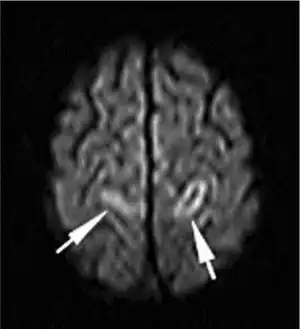

| A deep vein thrombosis in the right leg. There is striking redness and swelling. | |